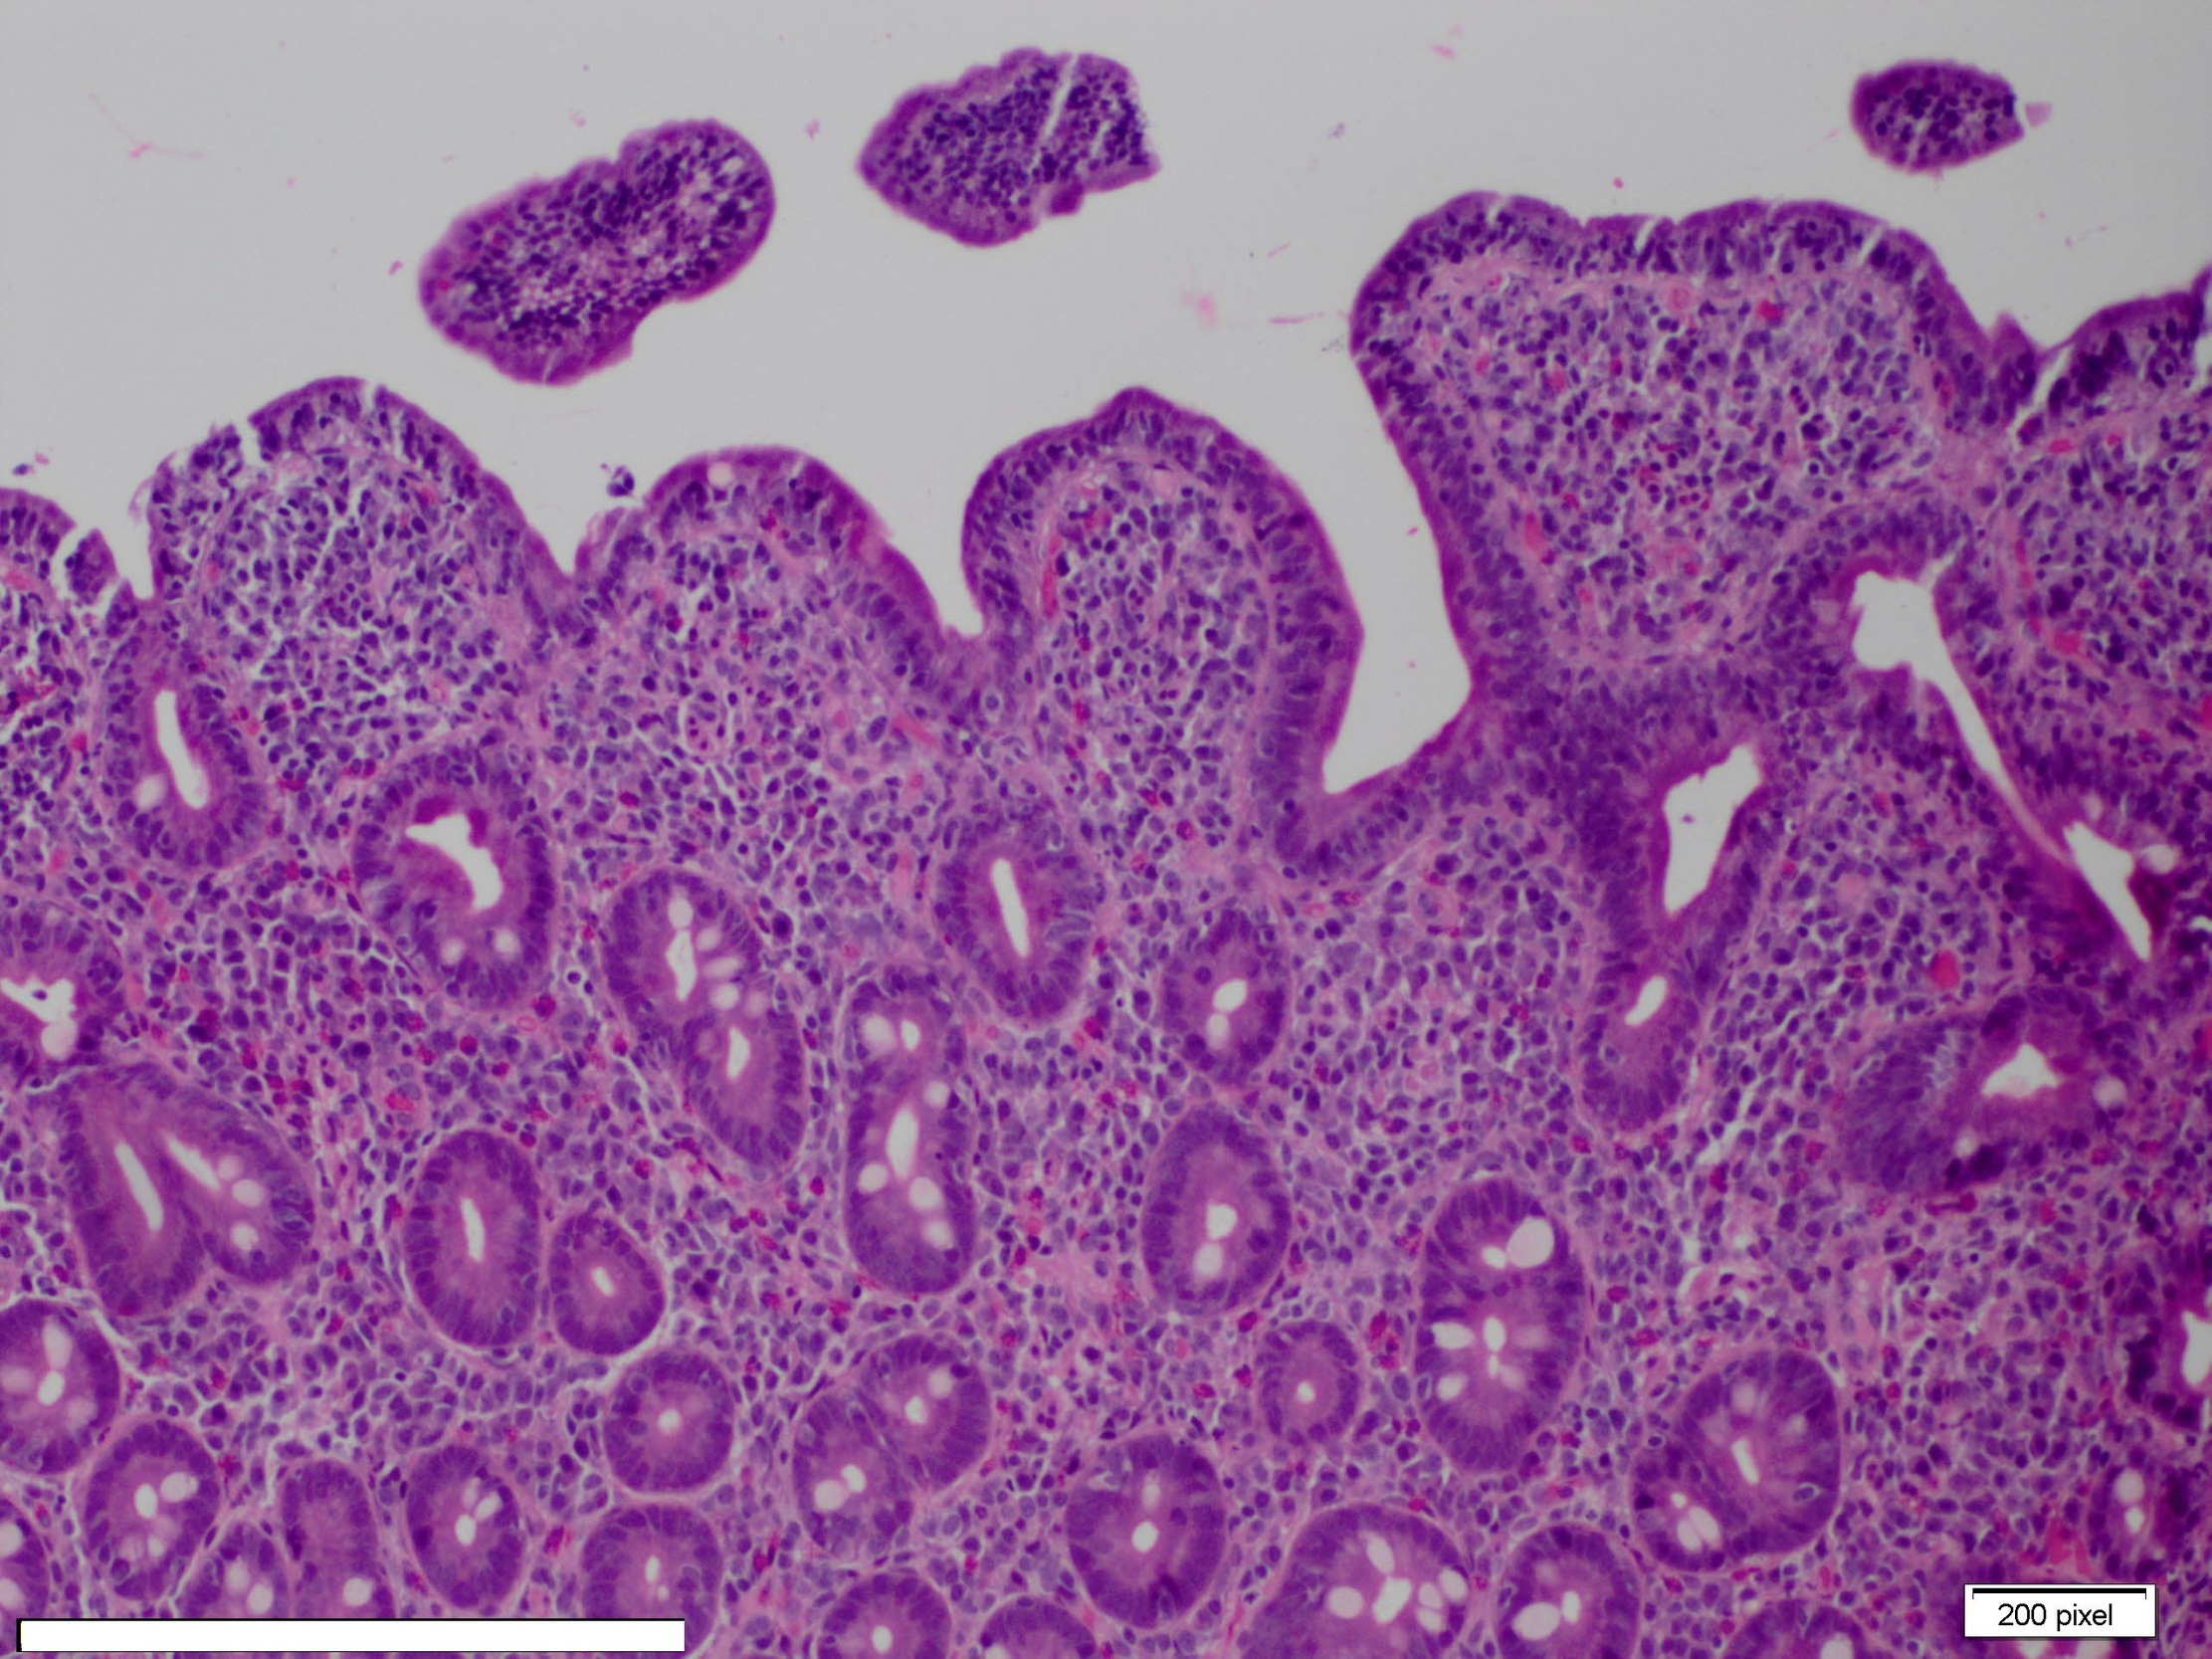

Her stool studies for celiac disease serology were also negative. She had a borderline positive ANA test at a titer of 1:160 with a homogeneous pattern. Homogenous pattern is a diffuse type of fluorescent pattern seen on indirect fluorescent antibody test. After two days in the hospital, she had a repeat endoscopy with duodenal biopsy, which revealed villous atrophy with attenuated and blunted villi with intraepithelial CD3 positive T lymphocytes (Images 1 and 2), suggestive of gluten enteropathy.

Olmesartan induced enteropathy is likely an immune-mediated condition that has been associated with a history of autoimmunity, presence of anti-nuclear antibodies, and presence of polyclonal intraepithelial lymphocytes.5 The histology associated with OSE is characterized by villous atrophy and increase in intra-epithelial lymphocytes such as CD3 and CD8 in the small bowel. Authors have also found this histology in other disorders such as Crohn’s disease, enteric infections, collagenous sprue, tropical sprue, common variable immunodeficiency, hematological malignancies and autoimmune enteropathy.1,2

Endoscopic examination with high definition scopes usually shows marked villous atrophy and flattening of duodenal villi.11 Other endoscopic findings found in OSE are nodularity in duodenal bulb 16 and duodenal ulcers,17 although normal duodenal patterns can also be found.18 Histopathologically flattening of villous pattern is the most common finding observed in various studies.1,2

Olmesartan induced enteropathy is an immune-mediated entity and the histology associated with this condition is characterized by villous atrophy and increase in intra-epithelial lymphocytes such as CD3 and CD8 in the small bowel. In this case study, endoscopy with duodenal biopsy also revealed villous atrophy with attenuated and blunted villi with intraepithelial T lymphocytes positive for CD3 cells. Other endoscopic findings found in OSE are nodularity in duodenal bulb and duodenal ulcers. In some cases, normal duodenal patterns have also been found with symptoms including diarrhea, generalized weakness and weight loss.18